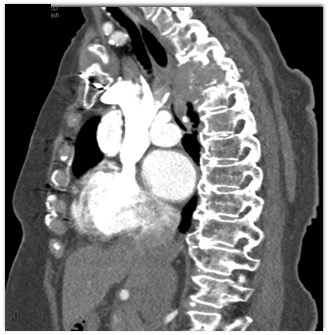

In this patient with back pain and shortness of breath the best dx is?

CTisus Quiz   CTisus Quiz

plasmacytoma

squammous cell carcinoma (SCC)

lymphoma

metastatic renal cell carcinoma